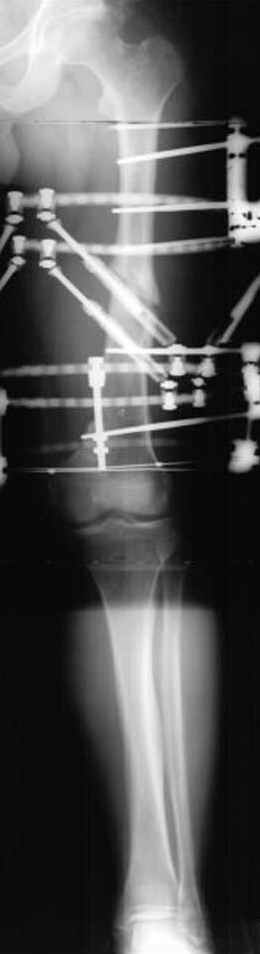

пластическая модель; и коррекция бедра аппаратом Илизарова.

Имею другие снимки тоже, получится как отчет о моей работе.

Отправитель: Evgueny Tschekashkin 23 Ноябрь 2004, 21:28

Почему не замена гвоздя с рассверливанием, а аппарат?

Отправитель: Alexander Chelnokov 23 Ноябрь 2004, 21:29

Попробую угадать - была инфекция?

Отправитель: Evgueny Tschekashkin 24 Ноябрь 2004, 21:09

хотя даже если бы и инфекция , то nail exchange с рассверливанием канала - вариант дебрайдмента) Я думаю, что последовательность развития событий:

Узкий к-м канал - тонкий гвоздь- усталостный перелом дистальных винтов - развитие нестабильности и как ее результат остеолиз вокруг гвоздя - деформация анатомической оси бедра. Похоже, что я понял почему аппарат, а не новый гвоздь:-)

• Re: Hip joint

Отправитель: Alexander Chelnokov 24 Ноябрь 2004, 21:11

ET> хотя даже если бы и инфекция , то nail exchange с рассверливанием канала -

ET> вариант дебрайдмента)

Да, но если, скажем, течет из инфицированных каналов запирающих винтов, да инфекция в дистальном метафизе бедра - устанешь сверлить.

Аппарат в таком случае средство из серии "тише едешь - дальше будешь".

ET> Я думаю, что последовательность развития событий:

[...]

ET> деформация анатомической оси бедра.

Да, наверно. Но если ничего другого нету, ту небольшую деформацию можно было устранить дистрактором одномоментно ввести другой гвоздь.

Отправитель: Evgueny Tschekashkin 24 Ноябрь 2004, 21:13

> Да, но если, скажем, течет из инфицированных каналов запирающих винтов, да инфекция в дистальном метафизе бедра - устанешь сверлить.

ЕТ-Теоретически это возможно, а практически трудно представить - все-таки уровень медицинского сервиса высок, поэтому вряд ли инфекционное воспаление может зайти так далеко.....

ET> Похоже, что я понял почему аппарат, а не новый гвоздь:-)

> Тогда делись догадкой скорей!

ЕТ - Изначально костно-мозговой канал бедра был узкий, дальнейшее его рассверливание ещё больше скомпрометирует прочность бедра( латеральный кортекс дистального отломка уже истончен), приведет к дефекту наружной стенки - хотя это только мои догадки - хотелось бы знать мнение Джолдаса о выбранной тактике.